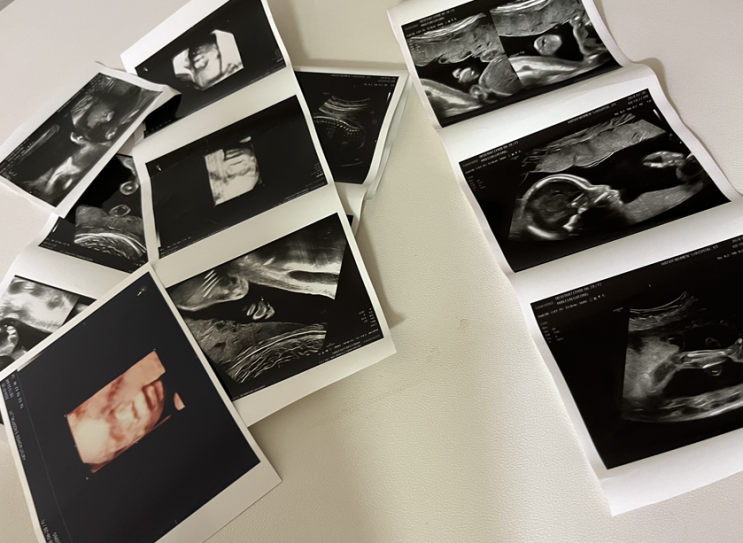

임신 21주 6일 햇빛병원 중기정밀초음파 후기 임산부저혈압 아스피린 복용 시작

안녕하세요~ 오늘 둘째 '기특이'의 중기정밀초음파를 보고 왔답니다. (21주 6일) 무려 5주만에 ...